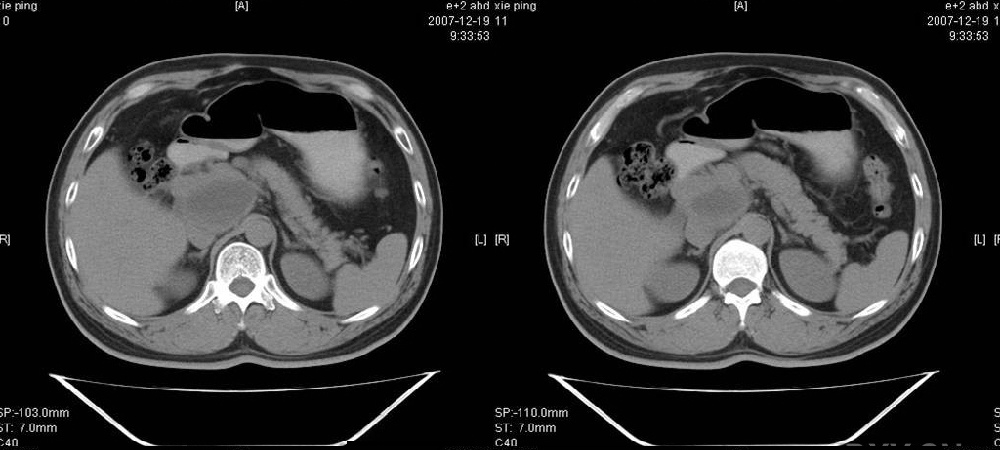

临床病史:患者,男,53岁,因反复上腹部饱胀不适2+月,在餐后或饥饿时明显,伴呃逆,无呕吐、呕血,无腹痛腹泻;2年前腹腔镜胆囊切除,否认肝炎、结核等病史。

十二指肠息室

pmrc显示病变与12指肠关系密切,与胆系不相通。

考虑十二指肠憩室。从影像上看,病变位于下腔静脉前胰头后方十二指肠内侧,肝尾叶受压,说明病变来源于后腹膜;胰胆管成像胰管和胆道未见扩张,总胆管中段受压未显示,上下段正常,所以不考虑来源与于肝尾叶和总胆管的囊肿。考虑为十二指肠憩室或小网膜囊肿。

楼上高手,本例的确是一例十二指肠憩室.

为什么口服的对比剂没有少量进入憩室里呢?我前段诊断过类似病例,对比剂少量进入憩室内,此病例是否口服对比剂时间短呢?